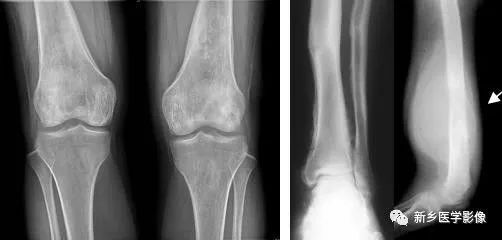

图7-17骨膜增生X线图像

a. 膝部X线正位片示两侧股骨下段内外侧均见与骨皮质表面平行的线状骨膜增生

b. 小腿下段X线正位片示胫骨下段内侧花边样骨膜增生

c. 股骨下段X线侧位片示局部骨质破坏、骨膜掀起,形成骨膜三角(↑),软组织肿块